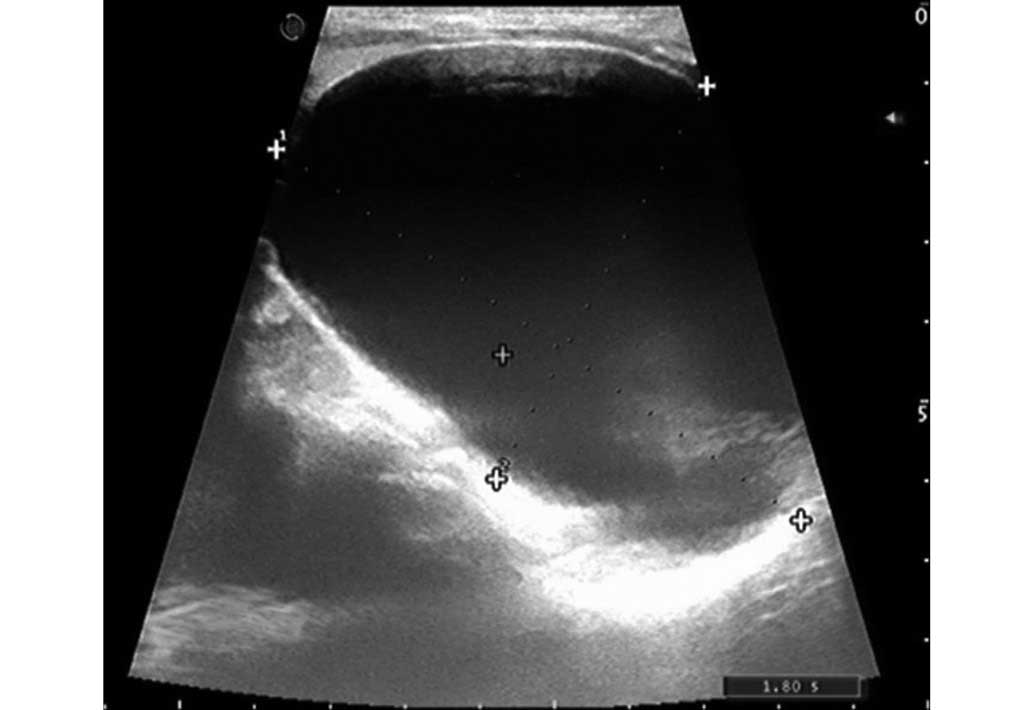

The physical examination revealed a palpable round-shaped mass in the right thyroid lobe. The ultrasound (Philips iU22; Philips Healthcare, Andover, MA, USA) showed a 8.4×5.7×3.6-cm cystic mass attached to the right thyroid lobe (Fig. 1). A neck and chest computed tomography (CT; LightSpeed Pro32 spiral scanner with a layer thickness of 5 mm; GE Healthcare Bio-Sciences, Pittsburgh, PA, USA) scan was performed with contrast media, which showed the presence of a large neck and mediastinal mass (9.0×6.0 cm) with no contrast enhancement, causing right anterolateral displacement of the large vessels and left anterolateral displacement of the trachea (Fig. 2). The serum calcium and PTH concentrations were measured and identified as normal, at 2.26 mmol/l (normal range, 2.03–2.54 mmol/l) and 37.98 pg/ml (normal range, 15–65 pg/m), respectively. A fine-needle aspiration biopsy (FNAB) was performed, and the content obtained from the cyst was a colorless crystal clear fluid, suggesting that the mass was a PC. The levels of PTH in the aspirated fluid were elevated (308 pg/ml; normal serum range, 10–65 pg/ml). A cytological examination of the material that was obtained following centrifugation of the fluid showed a few epithelial cells that possibly belonged to the parathyroid tissue. Based on the aforementioned findings, the diagnosis of the giant cyst was of a non-functional PC.

Figure 1.

Sagittal view of the thyroid gland on ultrasound, showing the presence of a 80-mm cystic nodule in the right lobe.